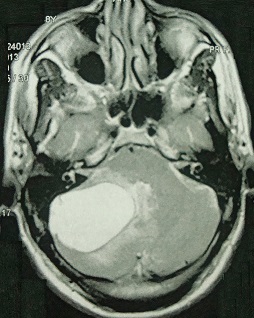

Simple intraparenchymal cyst of the cerebellum

We present a magnetic resonance imaging of a 38 old woman, admitted with clinical symptoms of expansive cerebellar lesion. No mural nodule and no enhancement after gadolinium injection were noted. She was operated upon and an anatomico-pathological diagnosis of a simple cyst was made. Cysts of the posterior fossa are common in the literature, but the simple cyst is rare. Considered in the differential diagnosis of these cysts: (hemangioblastoma, astrocytoma cystic, hydatid cyst ...). The postoperative course was uneventful after surgery.